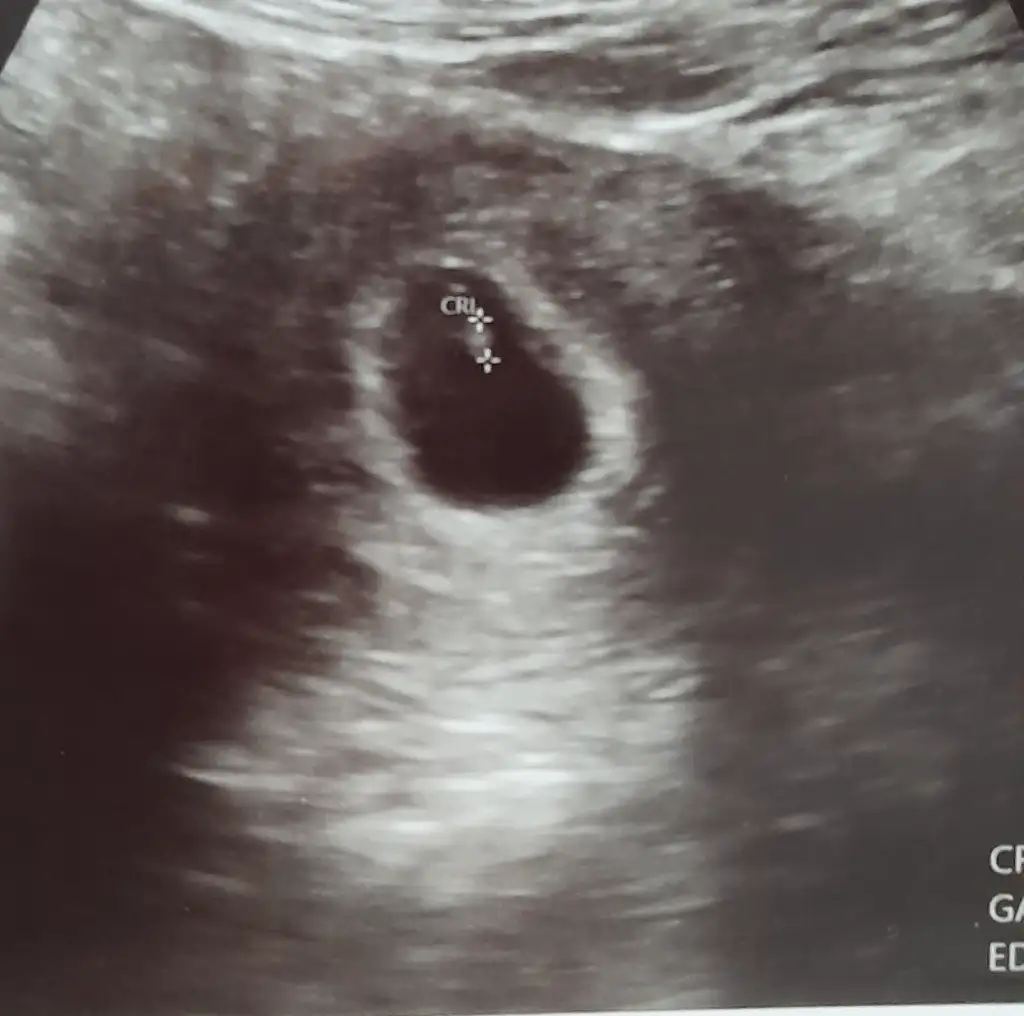

Bu kızımın 8 haftalık abdominal ultrason görüntüsü plasentası sağ da yani gerçekte sol da demek Ramzi teorisi tutuyor

Merhaba benimkine de bakar mısınız? 6+4 günlük bu ultrasonda karından bakıldı.